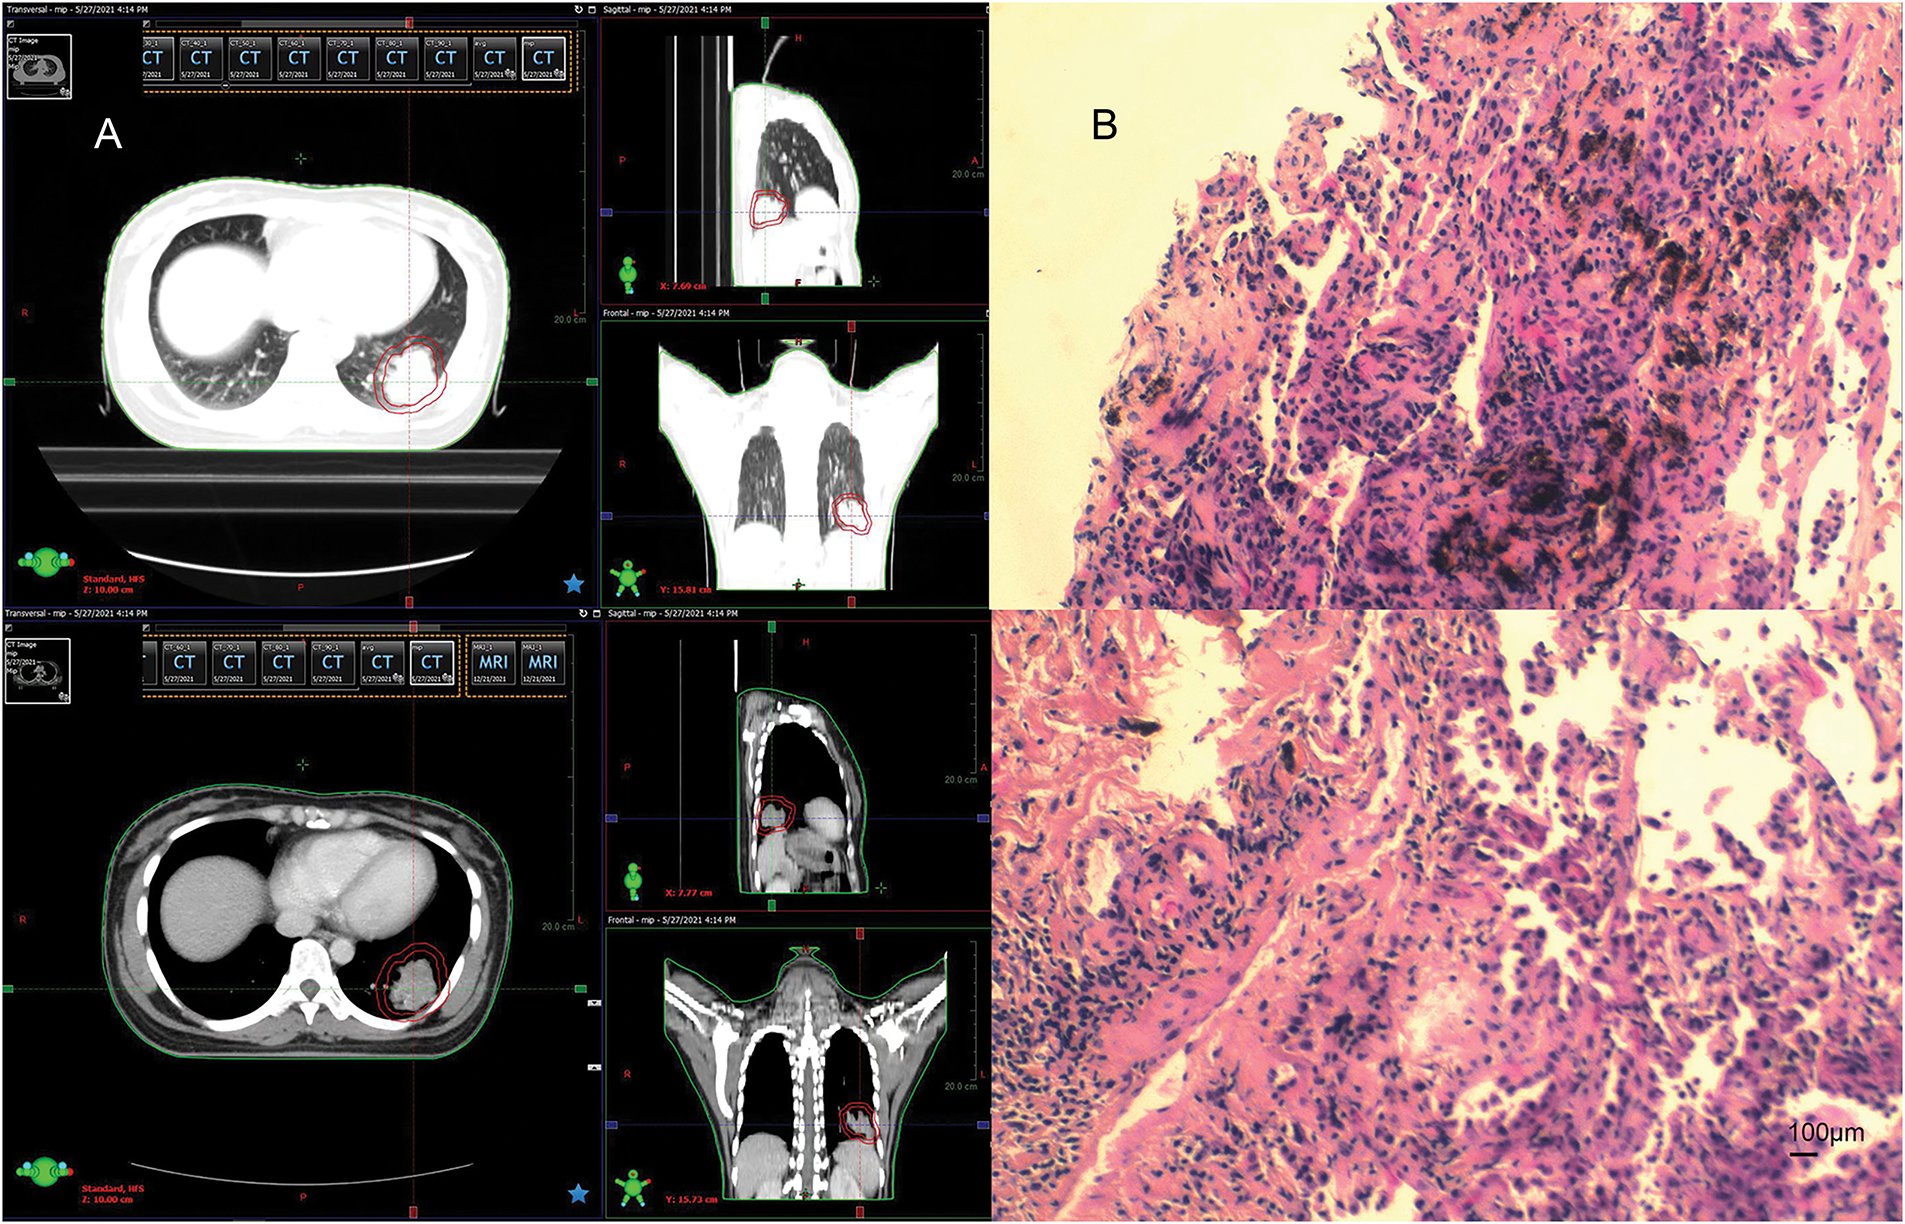

In April 2021, follow-up imaging of the chest enhanced computerized tomography revealed a slight enlargement of the pulmonary lesion; the rest of the systemic assessment was stable. Localized radiotherapy was initiated, with a treatment plan of intensity-modulated radiotherapy (IMRT) delivering a total dose of 64.4 Gray (Gy) in 14 fractions to the left lower lobe lesion (Fig. 2A). About one month after radiotherapy, the patient experienced a worsening cough and sputum production. In November 2021, a follow-up chest CT at a local hospital showed a significant enlargement of the left lower lobe lesion. The patient returned to our hospital for further examination. The findings were as follows: 1. A mass shadow in the lower lobe of the left lung, with a longest diameter of about 4.3 cm, is enlarged compared with prior imaging, FDG metabolism is slightly increased, post-treatment inflammatory changes are considered possible biopsy recommended if necessary; 2. right parietal lobe hypodense foci, FDG metabolism is reduced, the longest diameter of about 3.38 cm, slightly increased compared with the previous. A biopsy was performed again on the left lower lung lesion, and the pathologic result suggested chronic inflammation without evidence of cancer cells. Following departmental discussion, considering that surgery has both diagnostic and therapeutic functions, it was recommended that the left lower lung lesion be resected, the brain lesion be treated with radiotherapy, and immune maintenance therapy be discontinued. In January 2022, the patient underwent a radical resection of the left lower lobe of the lung, postoperative pathology (Fig. 2B): (left lower lung) chronic inflammation with histiocytic aggregation and multinucleated giant cell reaction, no residual cancer tissue, negative margin, lymph nodes (0/12). The cough symptoms of the patient were significantly relieved after the operation. Meanwhile, she completed radiotherapy for a brain lesion, with a total dose of 50 Gy in 10 fractions, targeting the probable gross tumor volume (PGTV) (Fig. 3A). One month after completion of brain radiotherapy, she developed right parietal headache and left-sided limb numbness, which worsened over time. In July 2022, the patient began to have convulsions in the left-sided limb, and the frequency gradually increased. In November 2022, the brain MRI showed that the right parietal lesion was revealed to be larger than before, with a longest diameter of about 4.0 cm. Referring to the management of lung lesions, the patient underwent a craniotomy for brain tumor resection in November 2022. The postoperative pathology (Fig. 3B): (right parietal lobe) cerebral edema with necrosis, neutrophilic and lymphocytic infiltration, mild proliferation of glial cells, and no definitive evidence of tumor. Similarly, the symptoms of headache and limb convulsion were significantly relieved after the operation.

Figure 2: Radiotherapy plan and pathologic findings after lung lesion enlargement. (A) First stage radiotherapy of the left lung region. (B) Biopsy pathology of the lung lesion in December 2021 (left inferior lobe lesion). Chronic inflammation of puncture tissue, fibrous hyperplasia, and local deposition of char (original magnification × 100, scale bar = 100 μm)

Figure 3: Radiotherapy plan and pathologic findings after brain lesion enlargement. (A) Second stage of the right parietal lobe region. (B) Postoperative pathology of the brain. Brain tissue edema with necrosis, focal neutrophil, and lymphocyte infiltration, mild glial cell proliferation, no definite neoplastic lesions (original magnification × 100, scale bar = 100 μm)